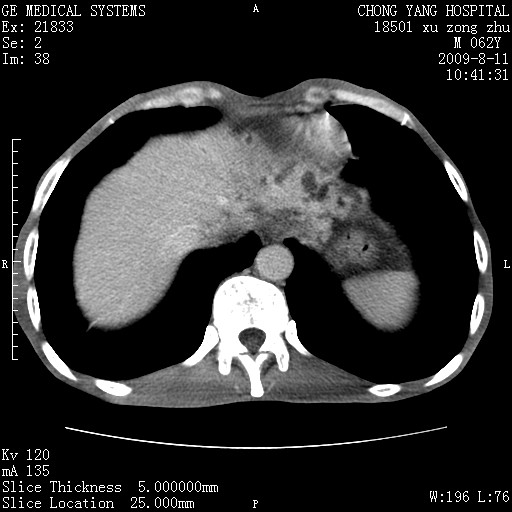

以下是引用杀毒软件在2009-8-11 16:35:00的发言:[br]肝内胆管扩张局限于左叶,胆管内有结石伴肝外胆管结石,胆管壁增厚呈弥漫性并发腹腔积液,胰腺边界模糊。[br][br]考虑---胆总管及肝内胆管结石继发胆管炎及胰腺炎,左肾下极囊肿,腹水。

以下是引用zjzjr在2009-8-11 17:35:00的发言:[br]肝内胆管扩张局限于左叶,胆管内有结石伴肝外胆管结石,胆管壁增厚呈弥漫性并发腹腔积液。[br][br]考虑---胆总管及肝内胆管结石继发胆管炎,左肾下极囊肿,腹水。